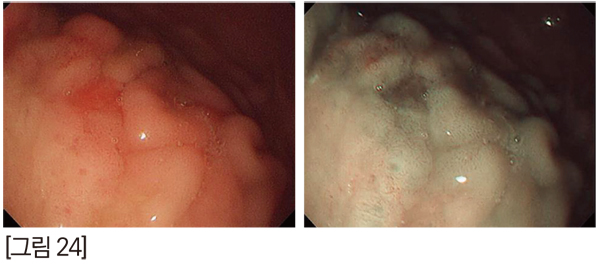

백색광으로 관찰했을 때 표면의 색은 균일하나 형태가 불규칙하여 악성으로 의심해 볼 수 있습니다. 하지만 NBI 영상에서 microvascular pattern과 microsurface pattern이 규칙적인 것으로 보아 악성 병변은 아닌 것으로 추정해 볼 수 있습니다. [그림 24]

Biopsy forcep을 이용하여 조직검사를 한 결과, gastritis로 진단되어 NBI 검사로 추정한 결과와 동일함을 확인할 수 있습니다. [그림 25]